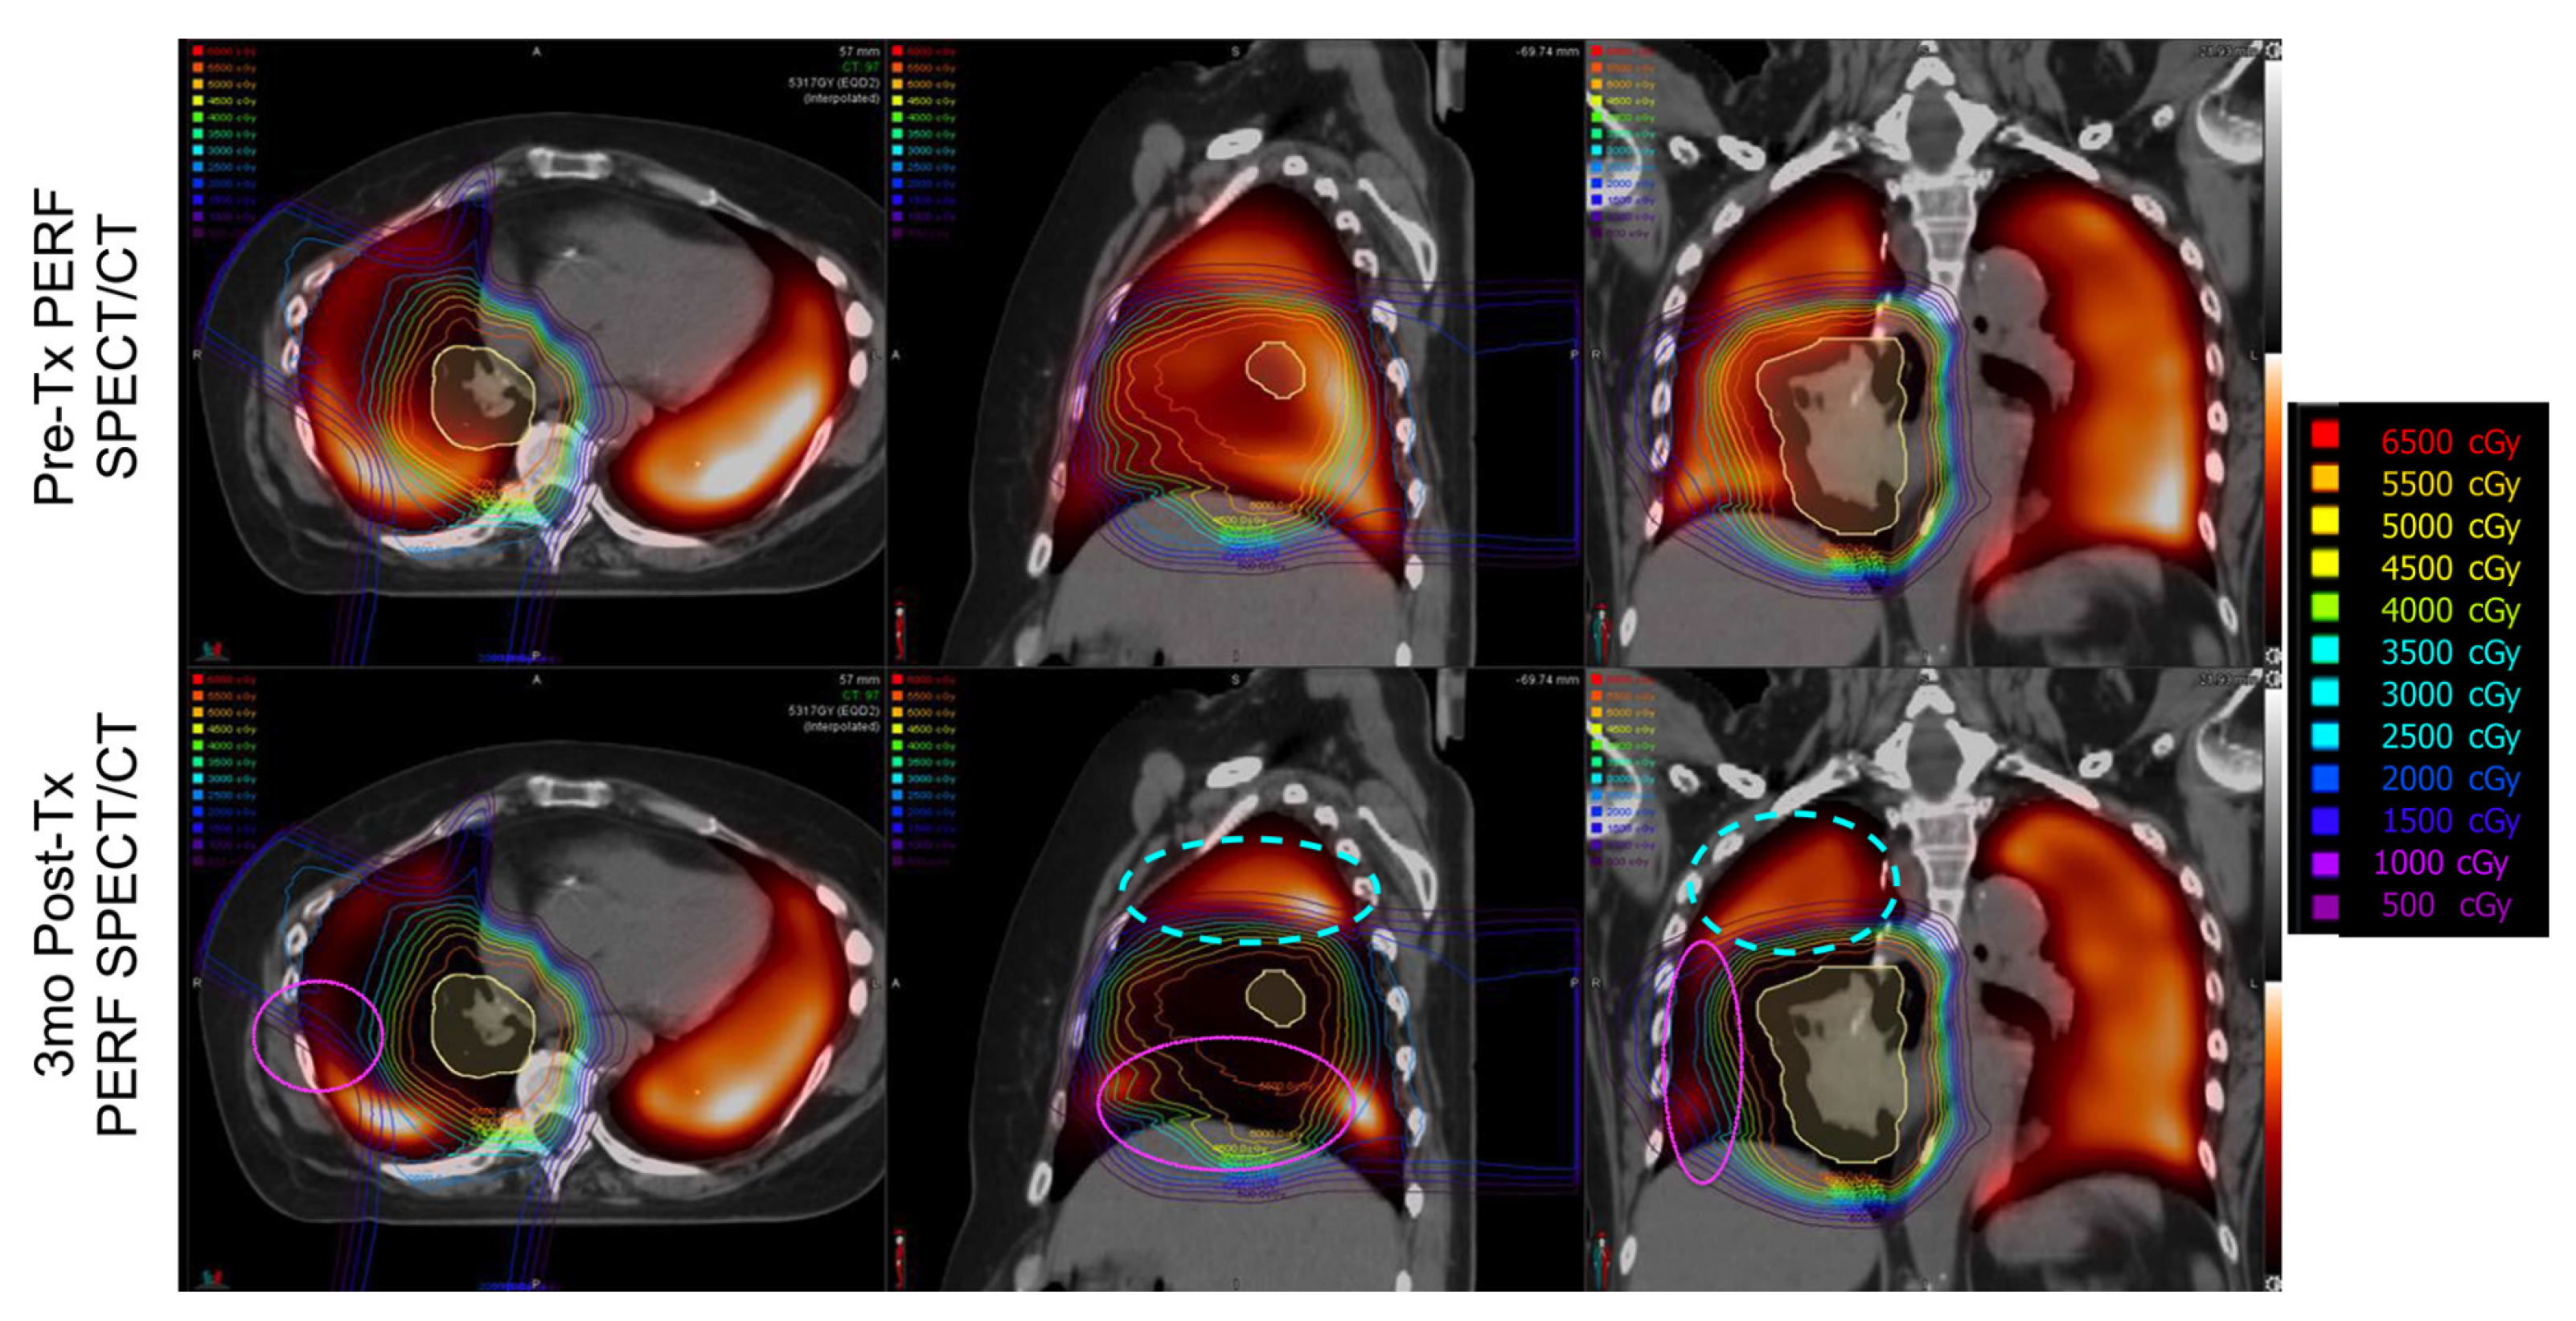

Imaging Results

4. Discussion

4.1. Changes in Kinetics

4.1.1. Ipsilateral Contours

4.1.2. Contralateral Lung